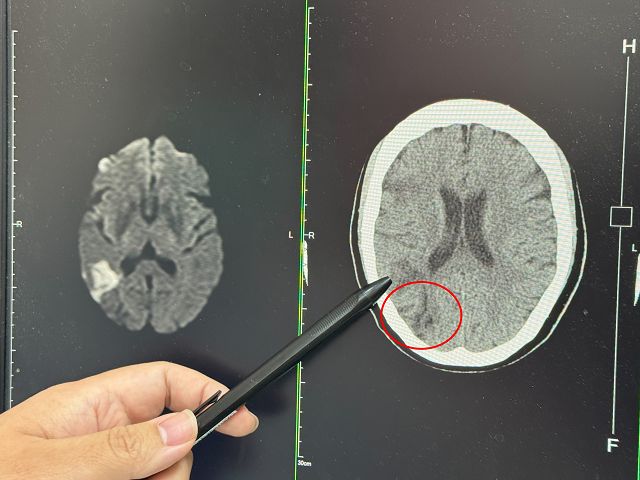

張峻誠說,聽完患者的描述,研判此症狀即是中風,先安排電腦斷層檢查,果然看到右邊中大腦動脈阻塞,為了確認阻塞範圍,進一步做核磁共振,詳細判讀後發現,婦人當時眼睛出現模糊時已經初次中風,只是比較幸運範圍較小,沒有出現手腳無力、無法行走的情形。

張峻誠指出,從患者檢查報告發現,對方有患有三高,尤其膽固醇嚴重超標,平時沒有好好控制,繼續追問患者,在第一次視力模糊後,不認為自己中風,後續皆沒有針對中風治療,才導致阻塞症狀加劇,幸運的是,阻塞範圍沒有擴大,否則恐怕會造成半身癱瘓。